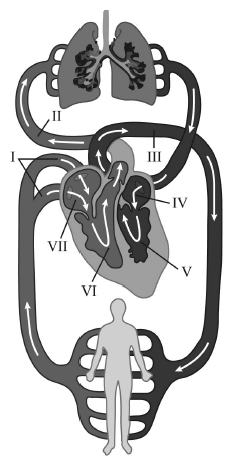

A figura apresentada ilustra os principais eventos circulatórios na espécie humana. Nessa figura, os números indicam as cavidades do coração e os grandes vasos da circulação sanguínea no homem. Considerando essa figura e os fenômenos que ocorrem durante o percurso do sangue na pequena e na grande circulação, julgue o próximo item.

O sangue não oxigenado é transportado até os pulmões pela artéria pulmonar, representada por II.